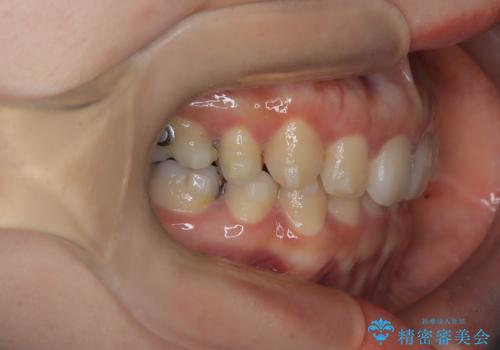

- 上下の歯の中心(正中)のズレと、口元の見た目を気にされて来院されました。精密な検査の結果、咬み合わせのバランスを整えながら、正中線を一致させる治療が必要と判断。患者様のご希望に合わせ、透明で目立ちにくいインビザライン(マウスピース矯正)による治療計画を立案しました。歯列全体を奥(遠心)へ移動させるためにゴムかけを併用。さらに、見た目を改善するため、既存の金属の被せ物をセラミッククラウンに交換することも治療計画に組み込みました。

今回の矯正治療では、透明なマウスピース型の装置インビザラインを使用しました。歯列を奥へ動かす遠心移動の効率を高めるため、患者様ご自身にゴムかけも行っていただきました。この併用によって、歯をより正確かつスムーズに動かすことができ、上下の歯の中心である正中線を一致させることが可能になりました。また、治療の最終段階では、以前から入っていた金属の被せ物を、天然歯に近い色合いのセラミッククラウンに交換。矯正治療と審美治療を組み合わせることで、機能的な咬み合わせの改善に加え、金属が見えない、より自然で美しい口元を獲得していただけました。